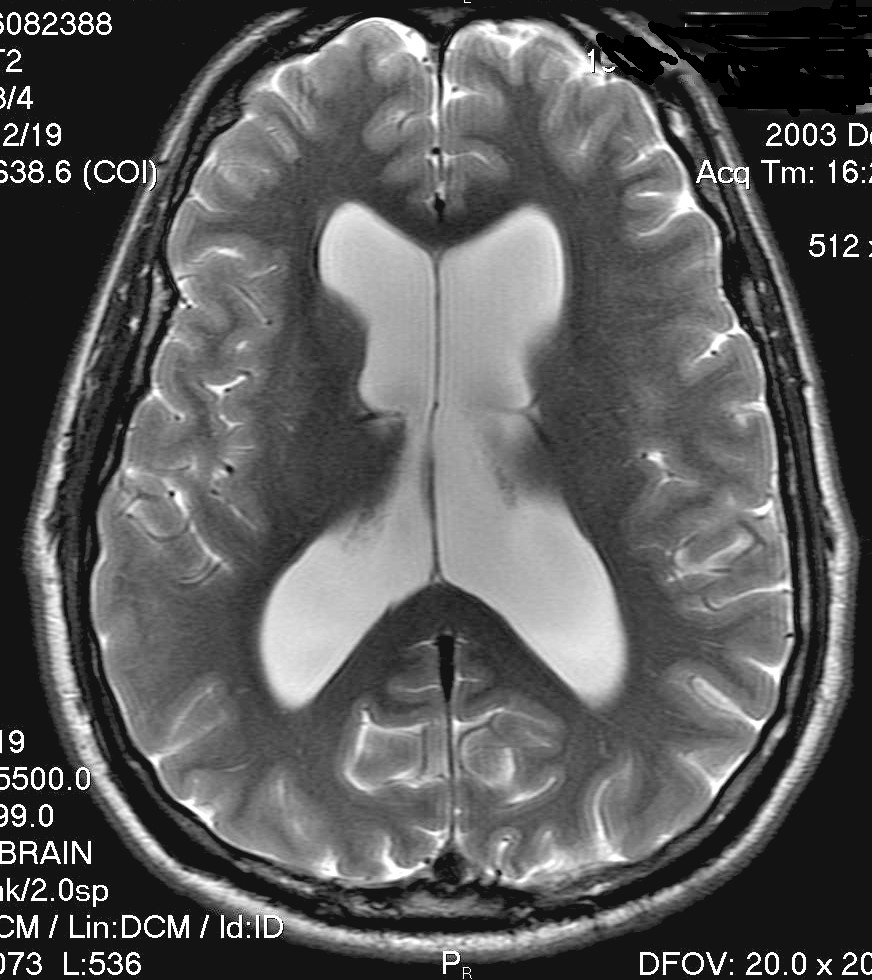

July 1992 pre-shunt          Dec 2003 OSV I                Nov 2007 Codman Medos SG

The brain produces about 20 ml of CSF per hour from the choroid plexus matter located within the lateral ventricles, and circulates this CSF through the third and fourth ventricles and around the surface of the brain. CSF acts to form a hydraulic support system for the brain and spinal chord, and helps move hormones and nutrients throughout the brain. It's more vital function, though, is in the regulation of venous blood pressure in the brain, and consequently ICP (intracranial pressure). This complex regulation impacts the function of higher order cognitive processes. Once circulated through the brain and spinal canal, CSF is reabsorbed via a complex network of tiny vessels called arachnoid villi. When CSF fluid is not reabsorbed at the same rate at which it is produced, due to a blockage (obstructive hydrocephalus) or insufficient absorption (communicating hydrocephalus) - swelling of the ventricles will ensue and exert increased pressure on the vital functions of the brain. MSN features a free interactive illustration of the human brain. At the bottom of this page, we include an MRI image of normal sized ventricles. During all of your care and treatment, it is critically important to have a close friend or relative you can count on - as I'm seen pictured eating with a long time friend above.